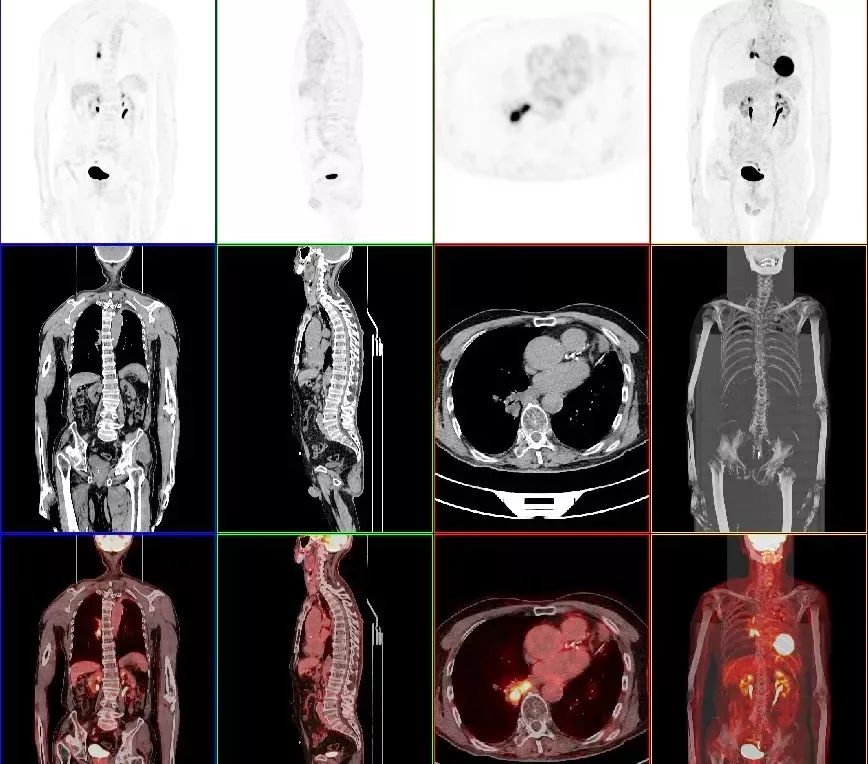

11月20日上午,“亳州市首台PET-CT开机仪式”在宝璋医院隆重举行。宝璋医院PET-CT正式开机,标志着我市医学影像诊断水平由组织形态学迈向分子水平的功能成像学,填补了亳州市核医学分子诊断领域的空白,为我市医疗卫生事业发展注入了新的活力。

PET-CT等于PET+CT,包含PET(功能分子影像)与CT(解剖影像)的最优化组合;即同时具有PET和CT的功能,但它绝不是二者功能的简单叠加,因为PET与CT优势互补,“1+1>2”。

PET-CT除了具备PET和CT各自的功能外,其独有的融合图像,将PET图像与CT图像融合, 可以同时反映病灶的代谢和形态学改变,可以早期诊断疾病的同时,明显提高诊断的准确性。